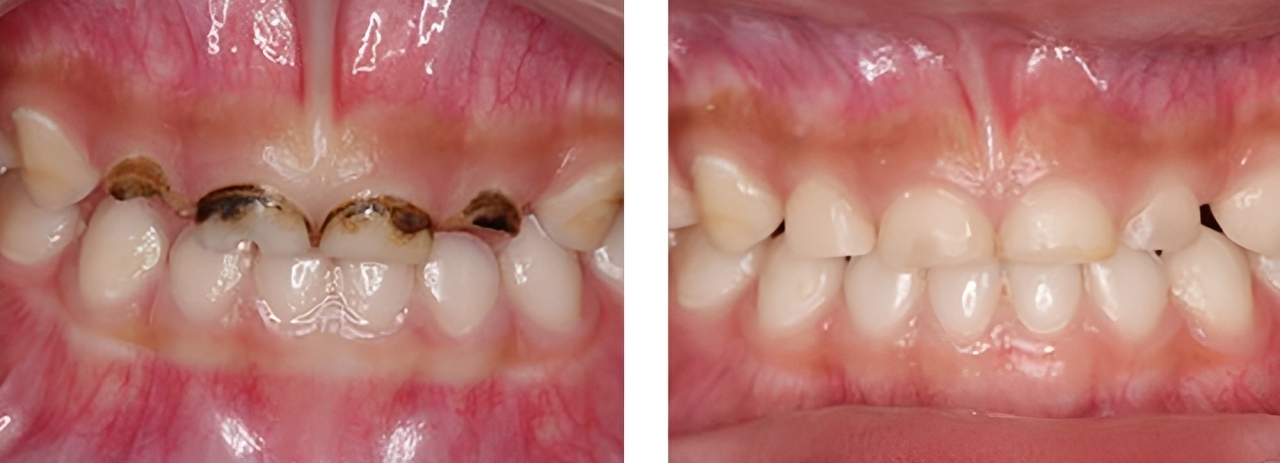

むし歯治療

術前

術後

| 治療内容 | 保険内でむし歯治療を行った |

|---|---|

| 治療期間・回数 | 1日・1回 |

| 費用 |

保険適用となります |

| リスク・副作用 | ・白いプラスチックでつくられているため経年劣化でプラスチックの部分は黄色や茶色に変色してしまいます。 |